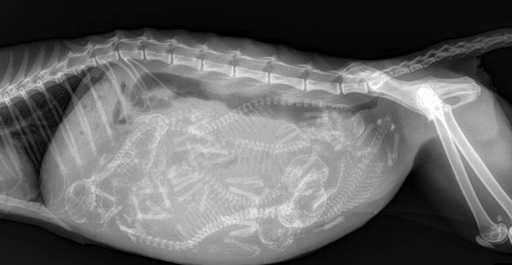

9. 怀孕的猫咪。

一些奇怪的X光照片,看完整个人都不好了……-9.jpg